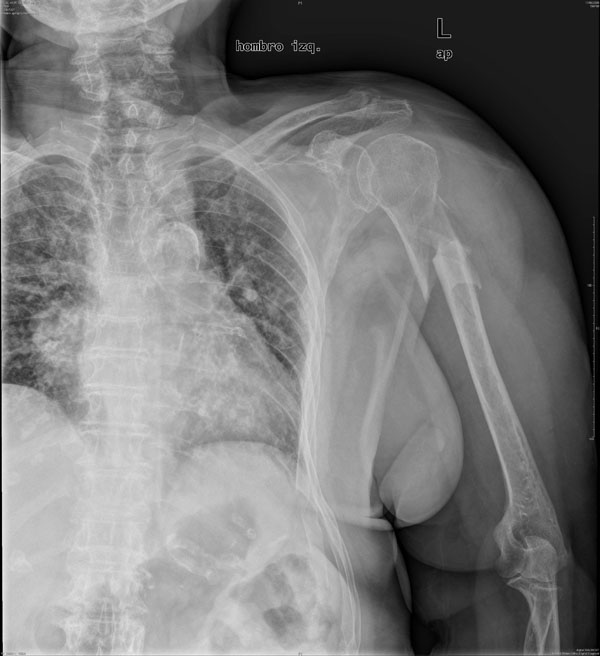

APR Luxación de hombro